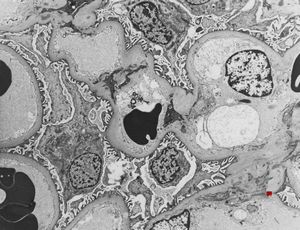

M,58y. | membranous glomerulopathy -early stage